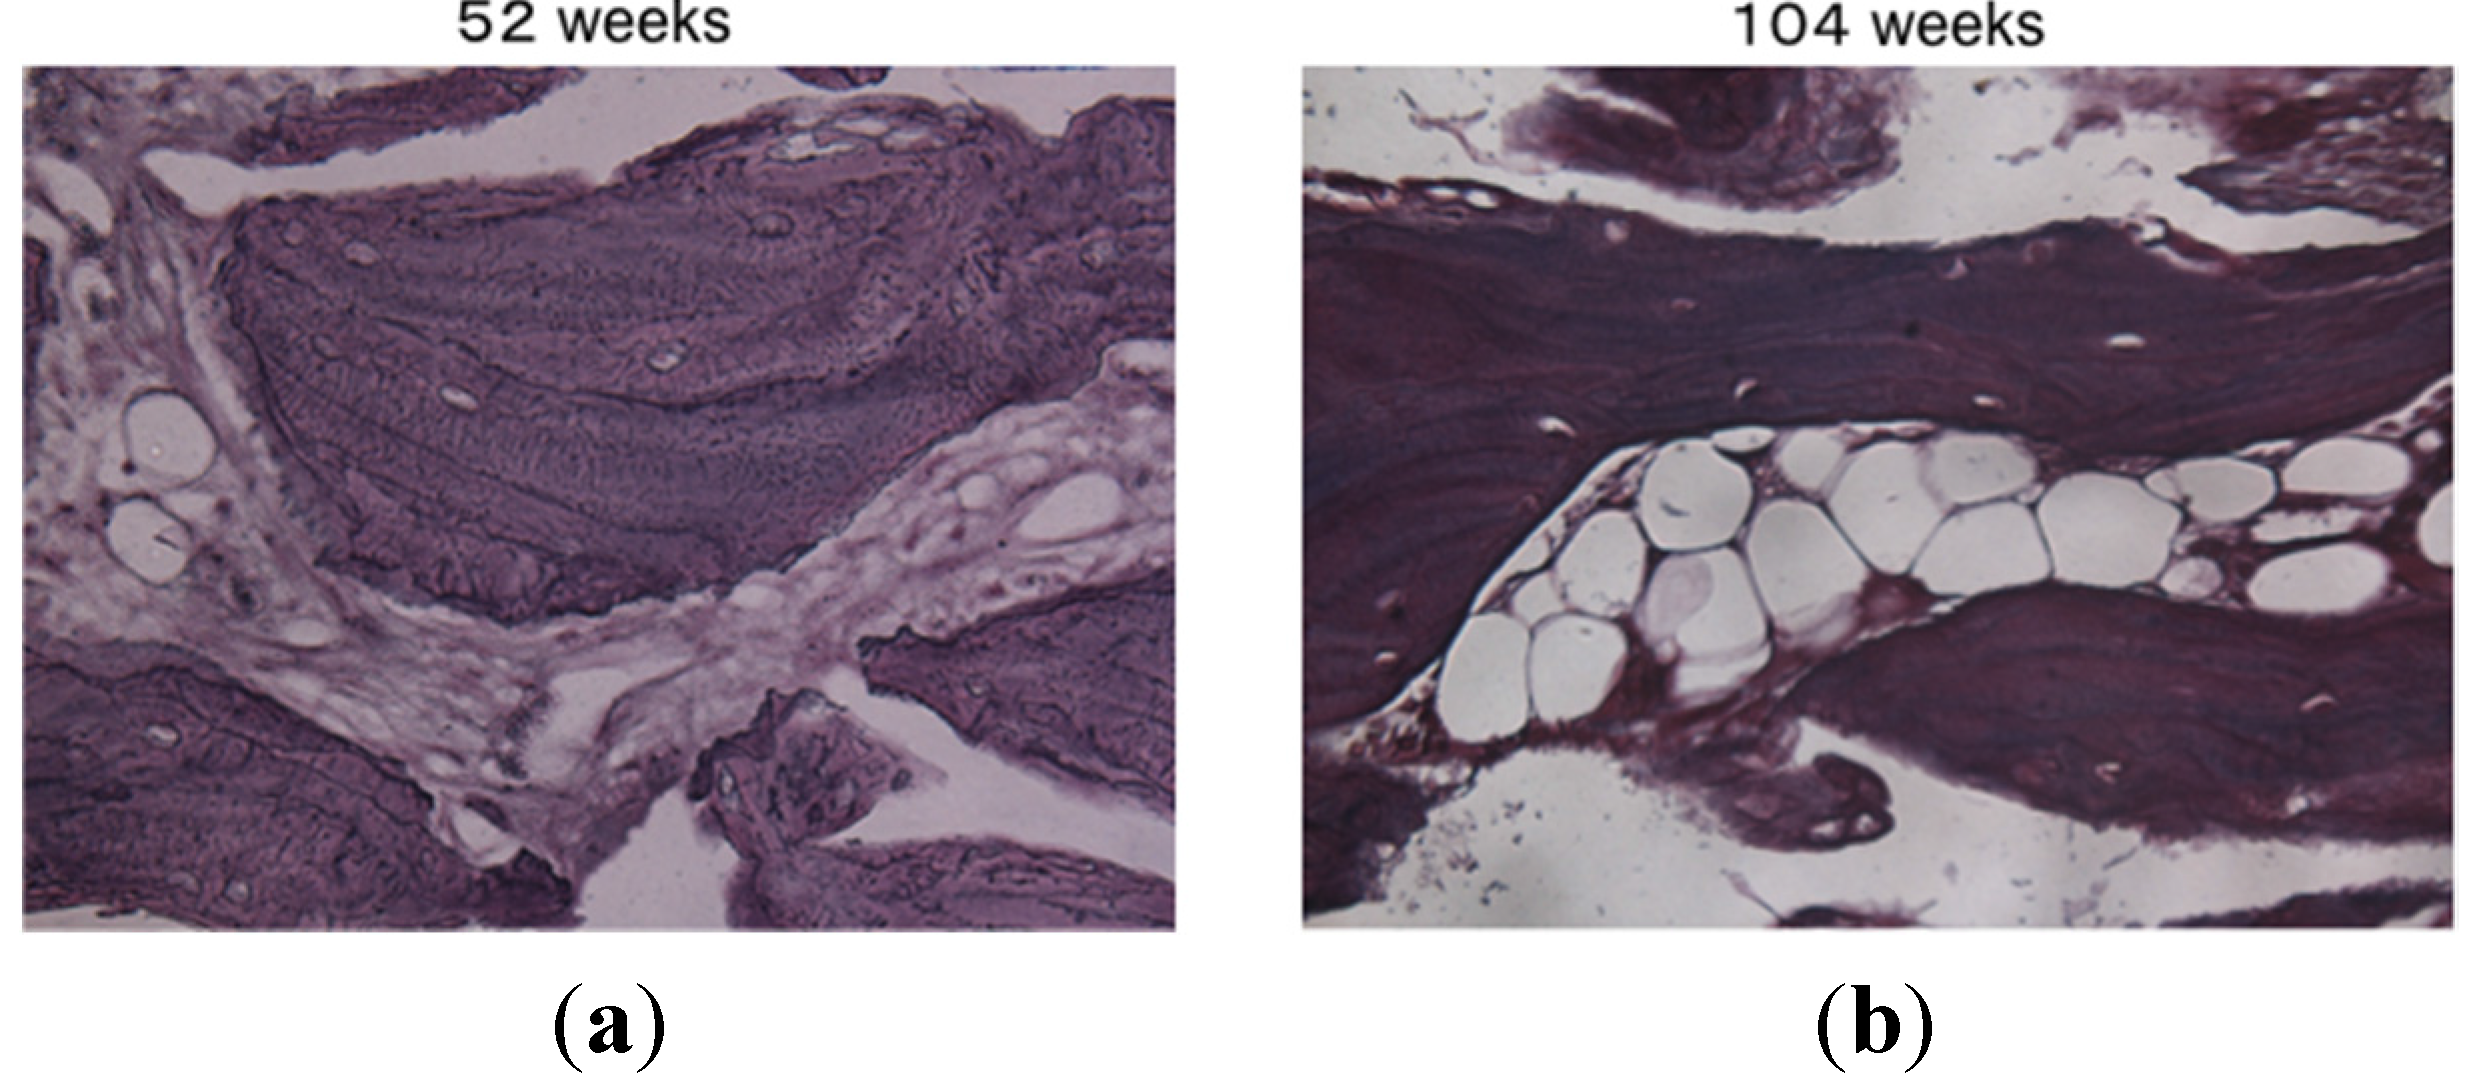

2. Results and Discussion

3.3. Bone Formation in Cortical and Medullary Bone Regions